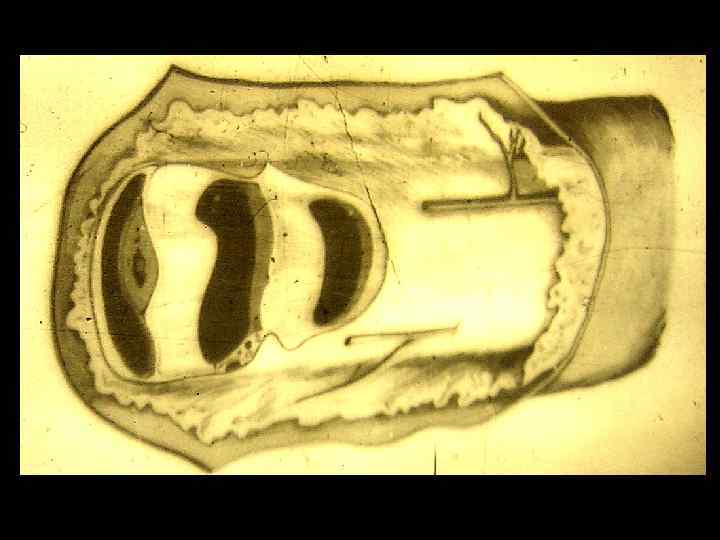

Объект и методы исследования в анатомии • Неживые объекты • Живые объекты - - - Вскрытие трупов и препарирование Бальзамирование Распилы частей тела и органов Метод инъекции и коррозии Изготовление сухих препаратов по В. Л. Груберу и Б. А. Шору и др. Просветление тканей органов Метод бьющей капли Макро - микроскопия Пластинация органов и трупов Гистотопография Световая и электронная микроскопия Соматоскопия Антропометрия Рентгеноанатомия (рентгенография, томография, электрорентгенография) - Эхолокация Компьютерная томография Магнитно-резонансная томография Эндоскопия Эксперименты на животных Математические и статистические методы